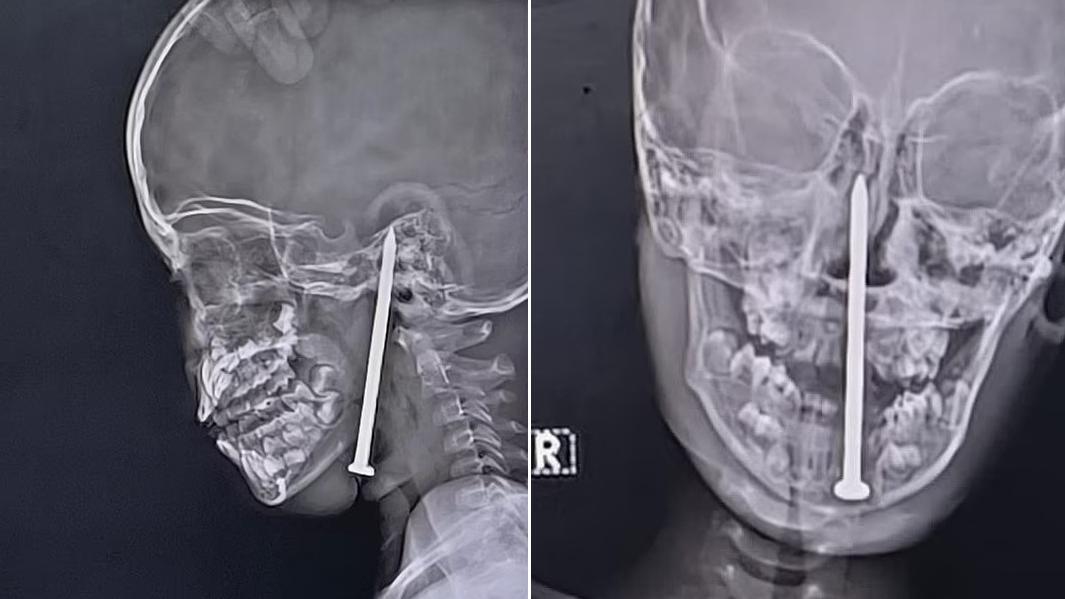

• X光檢查顯示,8厘米長鐵釘從下顎進入,直插男童腦部。(互聯網)

7歲童玩耍時跌倒 被8厘米鐵釘插進腦部 醫生施10小時高難度手術 跟死神搶人